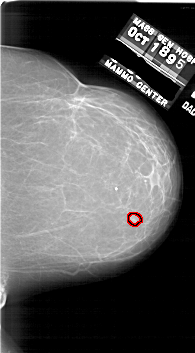

A_1748_1.RIGHT_MLO

RIGHT_MLO LINES 6616 PIXELS_PER_LINE 3721 BITS_PER_PIXEL 12 RESOLUTION 43.5 OVERLAY

FILE: A_1748_1.RIGHT_MLO.OVERLAY

TOTAL_ABNORMALITIES 1

ABNORMALITY 1

LESION_TYPE MASS SHAPE LOBULATED MARGINS CIRCUMSCRIBED

ASSESSMENT 3

SUBTLETY 3

PATHOLOGY BENIGN

TOTAL_OUTLINES 1

BOUNDARY